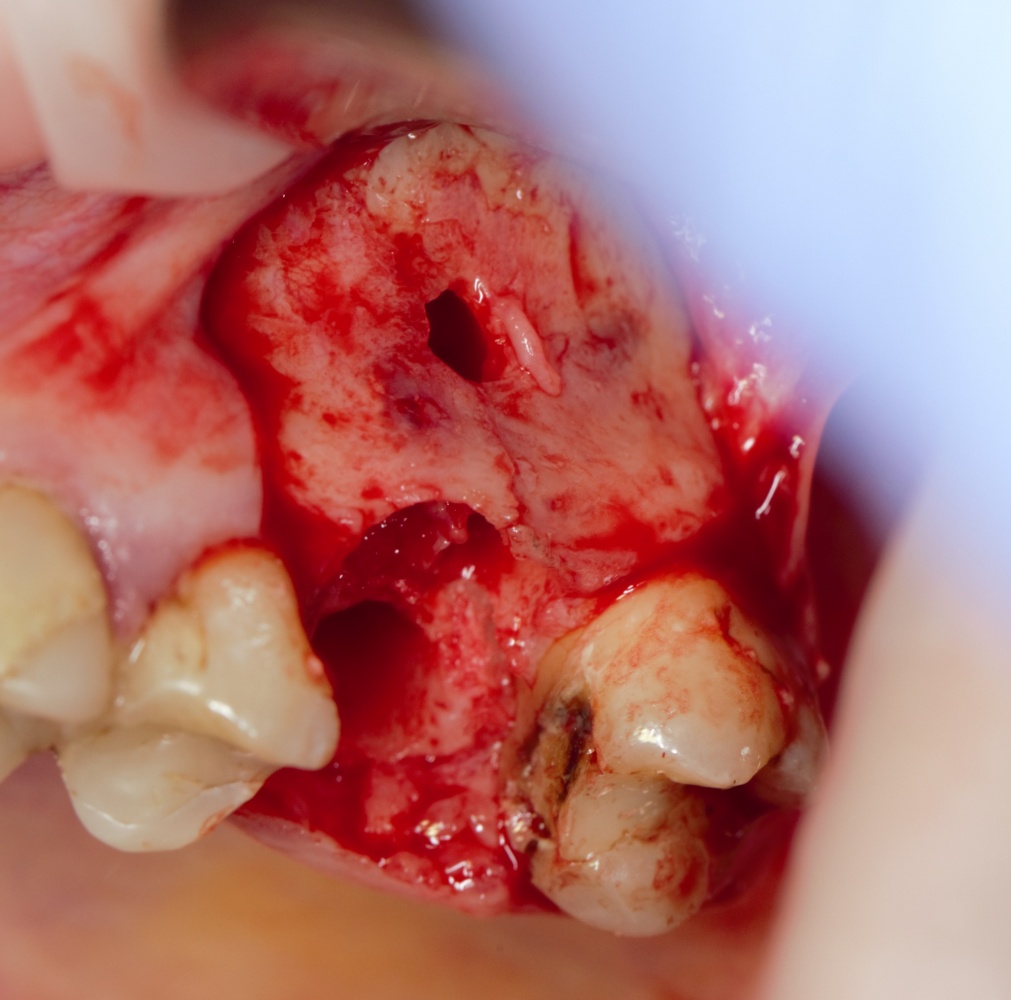

Кстати, обрати внимание на ширину альвеолярного гребня (левая картинка). Она чуть меньше 3 мм. Это объясняет, почему я засомневался в возможности установки имплантатов одновременно с остеопластикой. Понятно и без КЛКТ.

Наперво, мне нужно удалить разрушенный зуб и получить костный аутотрансплантат.

Для получения костного блока, мы открываем донорскую зону, наружную косую линию нижней челюсти.

Возвращаемся к основной операционной области. Еще раз посмотрим на альвеолярный гребень, поофигеваем от его ширины и моих грандиозных планов:

Я зафиксировал костный блок практически без адаптации на несколько винтов. Обрати внимание, что винты находятся в зоне, где не планируется установка имплантатов. Фиксация должна быть надежной, поскольку мне еще предстояла подготовка лунок для имплантатов. Трех винтов для этого вполне достаточно.

Дальнейшая адаптация костного блока свелась к сглаживанию острых краев. После чего я приступил к подготовке лунок и установке имплантатов.

Глянем на то, что получилось:

Осталось адаптировать костный блок (убрать острые края), проверить его фиксацию и, при необходимости, добавить винты. Десятисекундное дело.